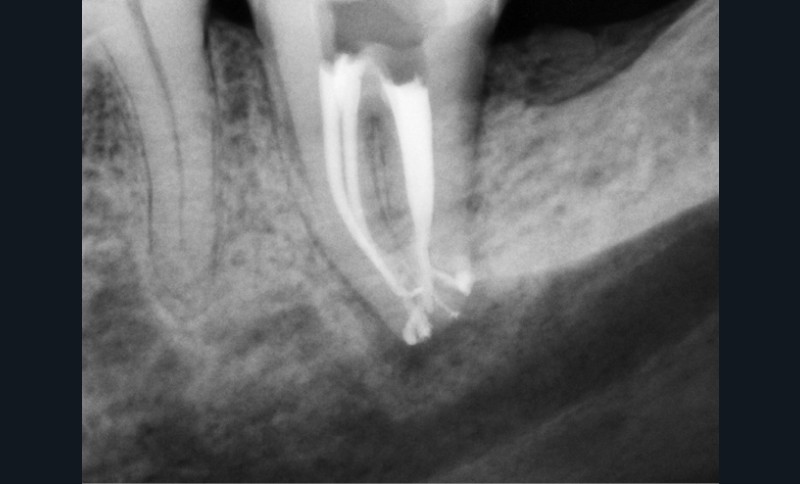

L’utilisation d’instruments en nickel titane, tels que le XP Shaper (FKG), le Vortex blue (Dentsply) ou le Profile (Dentsply), optimise la remontée des débris et s’inscrit dans cette nouvelle philosophie. En conséquence, la combinaison XP Shaper, XP Finisher et l’irrigation avec l’Er:YAG semblent optimiser nos traitements [44,45].

Le passage du laser est répété plusieurs fois, en début, au milieu et en fin de préparation. Un protocole peut alors être proposé : 40 mJ ; 20 Hz (fig. 7). L’utilisation de biocéramiques Bioroot (Septodont) ou Total Fill R (FKG) permet de sceller le système ainsi nettoyé, en assurant une action biologique de longue durée [46] (fig. 8a à c).